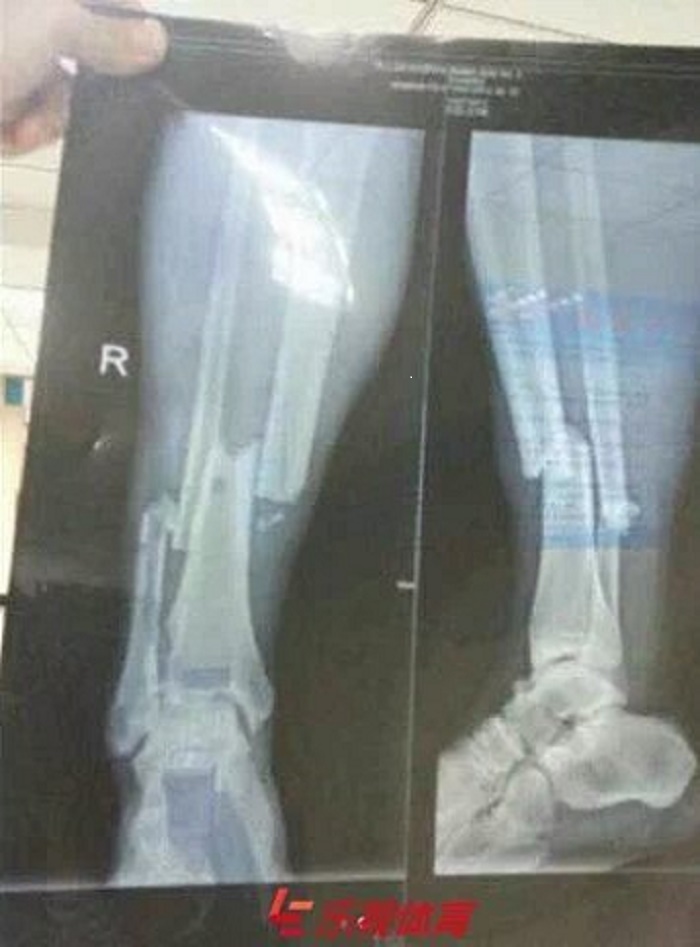

Title : Horrible La Radio De La Jambe Cassee De Demba Ba Source : www.beinsports.com Open New Window

Title : Demba Ba S Broken Leg X Ray Revealed Goal Com Source : www.goal.com Open New Window

Title : L Horrible Radio Du Tibia De Demba Ba Apres Sa Blessure Goal Com Source : www.goal.com Open New Window